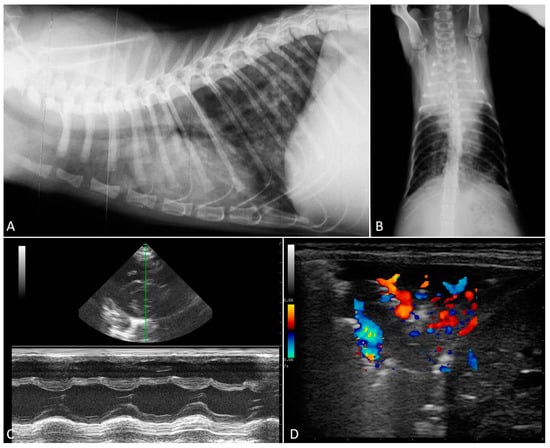

2.2. Radiographic Findings

2.3. Echocardiography

- Febo, E.; Crisi, P.E.; Traversa, D.; Luciani, A.; Di Tommaso, M.; Pantaleo, S.; Santori, D.; Di Cesare, A.; Boari, A.; Terragni, R.; et al. Comparison of clinical and imaging findings in cats with single and mixed lungworm infection. J. Feline Med. Surg. 2019, 21, 581–589. [Google Scholar] [CrossRef]

- Genchi, M.; Ferrari, N.; Fonti, P.; De Francesco, I.; Piazza, C.; Viglietti, A. Relation between Aelurostrongylus abstrusus larvae excretion, respiratory and radiographic signs in naturally infected cats. Vet. Parasitol. 2014, 206, 182–187. [Google Scholar] [CrossRef]

- Lacava, G.; Zini, E.; Marchesotti, F.; Domenech, O.; Romano, F.; Manzocchi, S.; Venco, L.; Auriemma, E. Computed tomography, radiology and echocardiography in cats naturally infected with Aelurostrongylus abstrusus. J. Feline Med. Surg. 2017, 19, 446–453. [Google Scholar] [CrossRef]